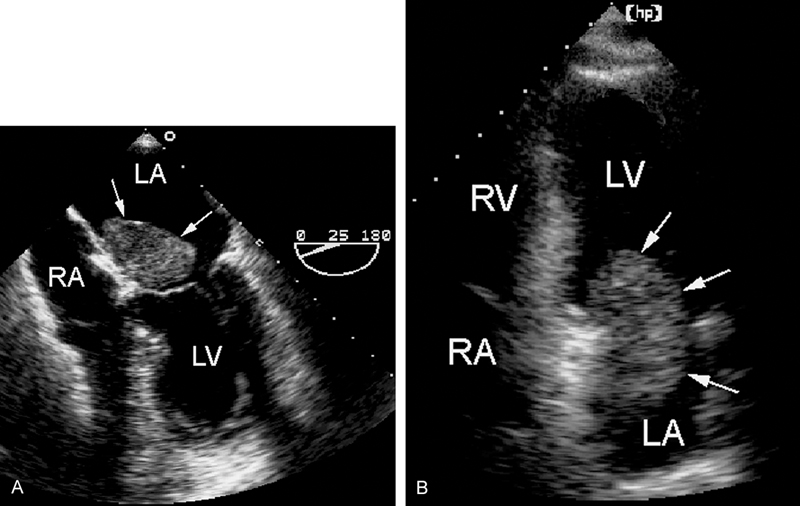

فحوصات تشخيصية لبعض امراض القلب والشرايين التاجية